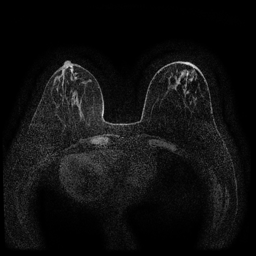

Magnetic field strength. 3T scanners offer higher magnetic field strength, improving signal-to-noise ratio (SNR) and image resolution for sharper, more detailed images [24]. However, they are more prone to artifacts, heating effects, and signal loss, especially around metal implants [5]. As such, our proposed dataset involving this spurious signal features a non-local spurious signal that influences the entire image rather than a localized region. An example set of images obtained from 1.5T and 3T devices are provided in Figure 3, showing that it is visually not possible to distinguish 1.5T MRIs from the 3T ones.

Vertical orientation. Different from magnetic field strength, which affects the entire image globally, vertical orientation is a local feature that only alters the spatial arrangement of structures within the image. This transformation does not modify the underlying tissue characteristics or signal properties but instead introduces artificial correlations that models may exploit as shortcuts.